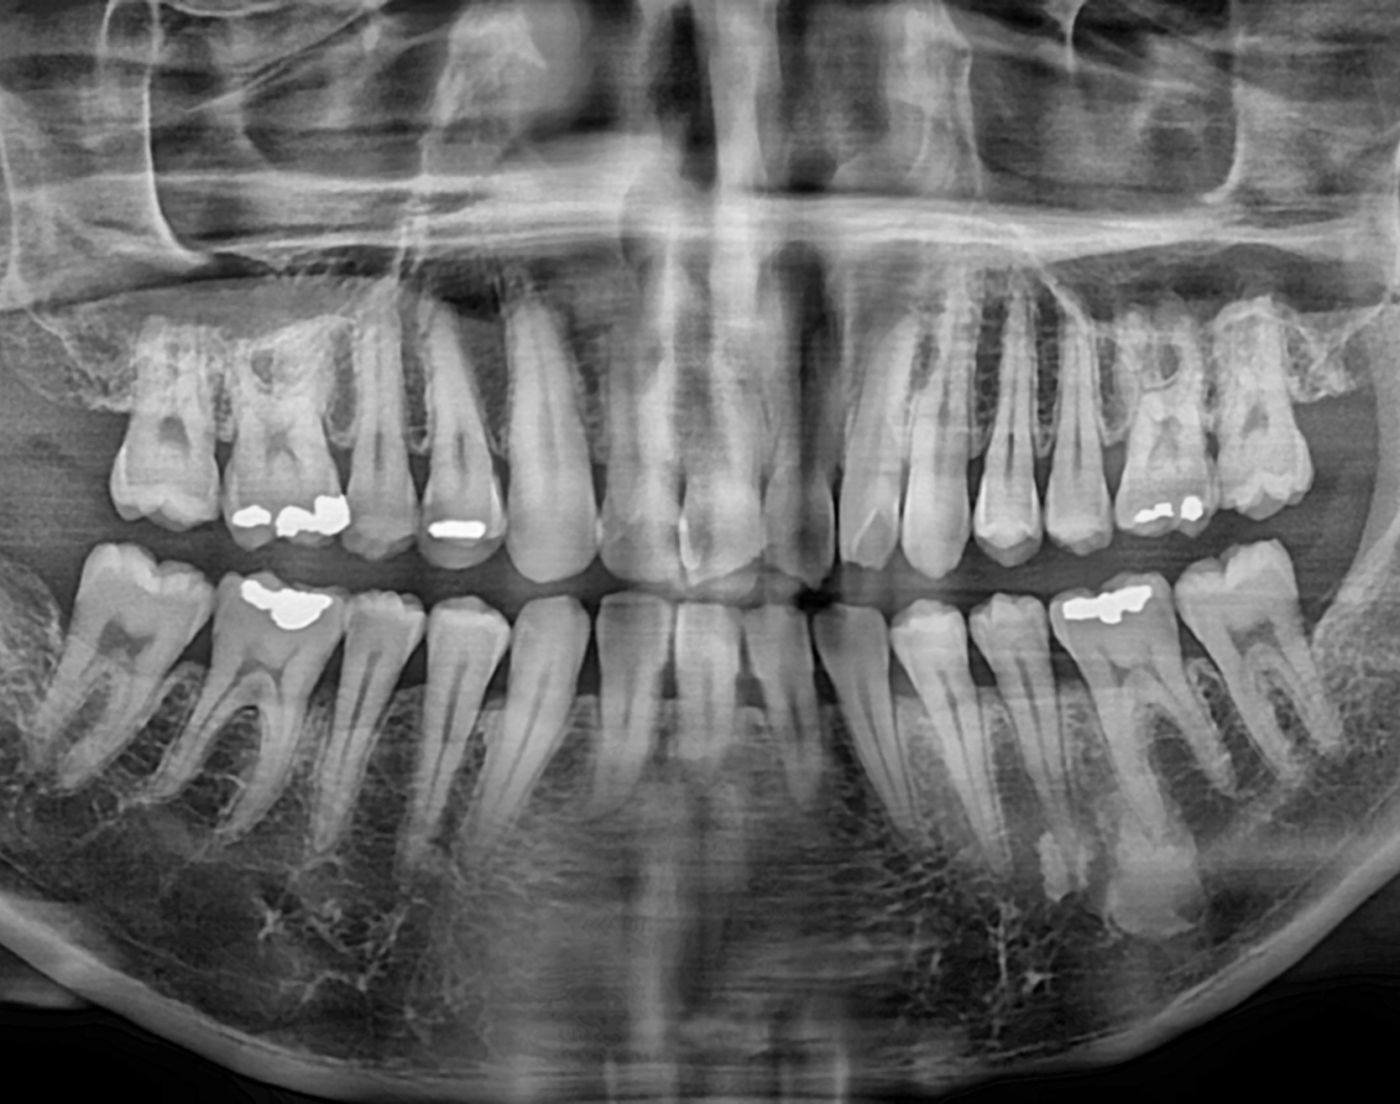

얼마전 자전거 타다가 넘어져서 앞니가 살짝 부러졌습니다.

진짜 엄청 많이 부러진것도 아니고 끝부분만 뾰족하게 부러졌어요.

그래도 생니가 부러졌으니 아프죠. 아프니까 동네 치과에 갔어요.

뭐 이런저런 설명을 하고 신경치료 하고 크라운을 씌우자고 하네요.

어쨋든 그렇게 치료를 받고 와서 내가 받을 치료가 뭔지 검색해보니 치아를 많이 삭제하고 뭘 씌우는 치료라는걸 알게 됐습니다. 아 나는 그냥 레진으로 떼우는거 생각하고 갔는데 뭔가 과한 치료를 받은거 같아요. 그래서 다른 치과에 가서 검진 받아보니 이전 상태는 모르겠는데 이미 신경치료를 받아버려서 치아 3개는 살릴 수가 없데요. 그래서 신경치료도 알아보니 이게 치료가 아니라 신경을 제거하는 시술이래요.

아니 그럼 왜 그게 이름이 신경치료인건데요; 신경 제거술이라고 하면 좀 고민하고 생각해본다고 했을 여지가 있는데 치료라고 하니까 별 생각 없이 아 아픈데 치료해주나보다 하고 ㅇㅋ 하고 치료받았죠. 처음부터 생니 갈아버릴 생각 전혀 없었는데 일이 이렇게 커지니 당황스럽습니다.

물롱 의사 선생님 진단이 정확하고 신경치료가 필요하고 크라운 씌우는게 맞을 수도 있어요. 그런데 저는 거기서 진단 받고 다른 치과도 가서 또 진단 받고 여러 의견을 구할 생각이었는데 당장 아프니까 치료라고 해서 받은 제거술이 발목 잡네요. 이제는 빼박 앞니 세개 무조건 갈아야한답니다. 후……. 진짜 화가 납니다. 왜 네이밍이 신경치료인지 모르겠어요. 친구들에게 이야기 하니 다들 신경치료 = 신경 제거인지 몰랐대요. 당연히 저처럼 모르죠. 경험자가 아닌이상……. 누가 그런것까지 공부하고 병원을 가요.

이제는 선택의 여지가 없이 앞니 3개 무조건 갈아서 크라운 씌우게 생겼습니다. ㅠㅠ